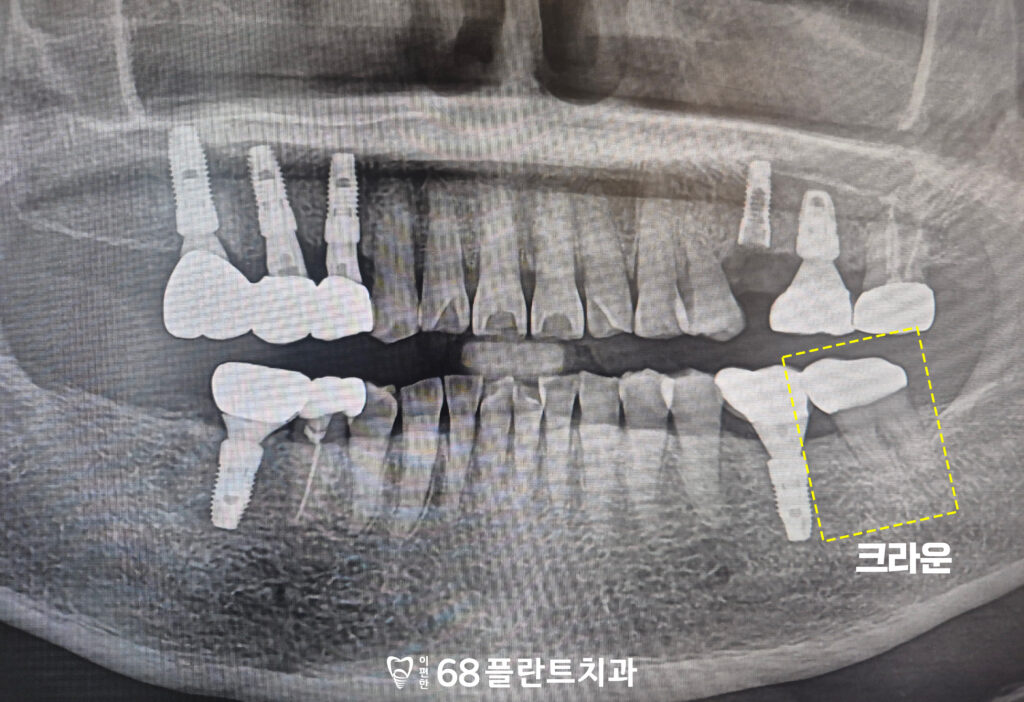

왼쪽 아래 치아는

크랙과 교모가 관찰되었지만

뚜렷한 통증이나 불편감이 크지 않아,

신경치료 없이 크라운 치료만으로

치아를 보호하기로 결정하였습니다.

크라운을 통해 약해진 치아를 감싸

외부 자극으로부터 보호하고,

크랙의 추가 진행을 예방하여

기능적으로도 안정적인

상태를 유지할 수 있도록

치료를 진행하였습니다.

불편함 없이 괜찮으시다 하셔서

영구 접착 후 전체적인

치료를 마무리해 드렸습니다.